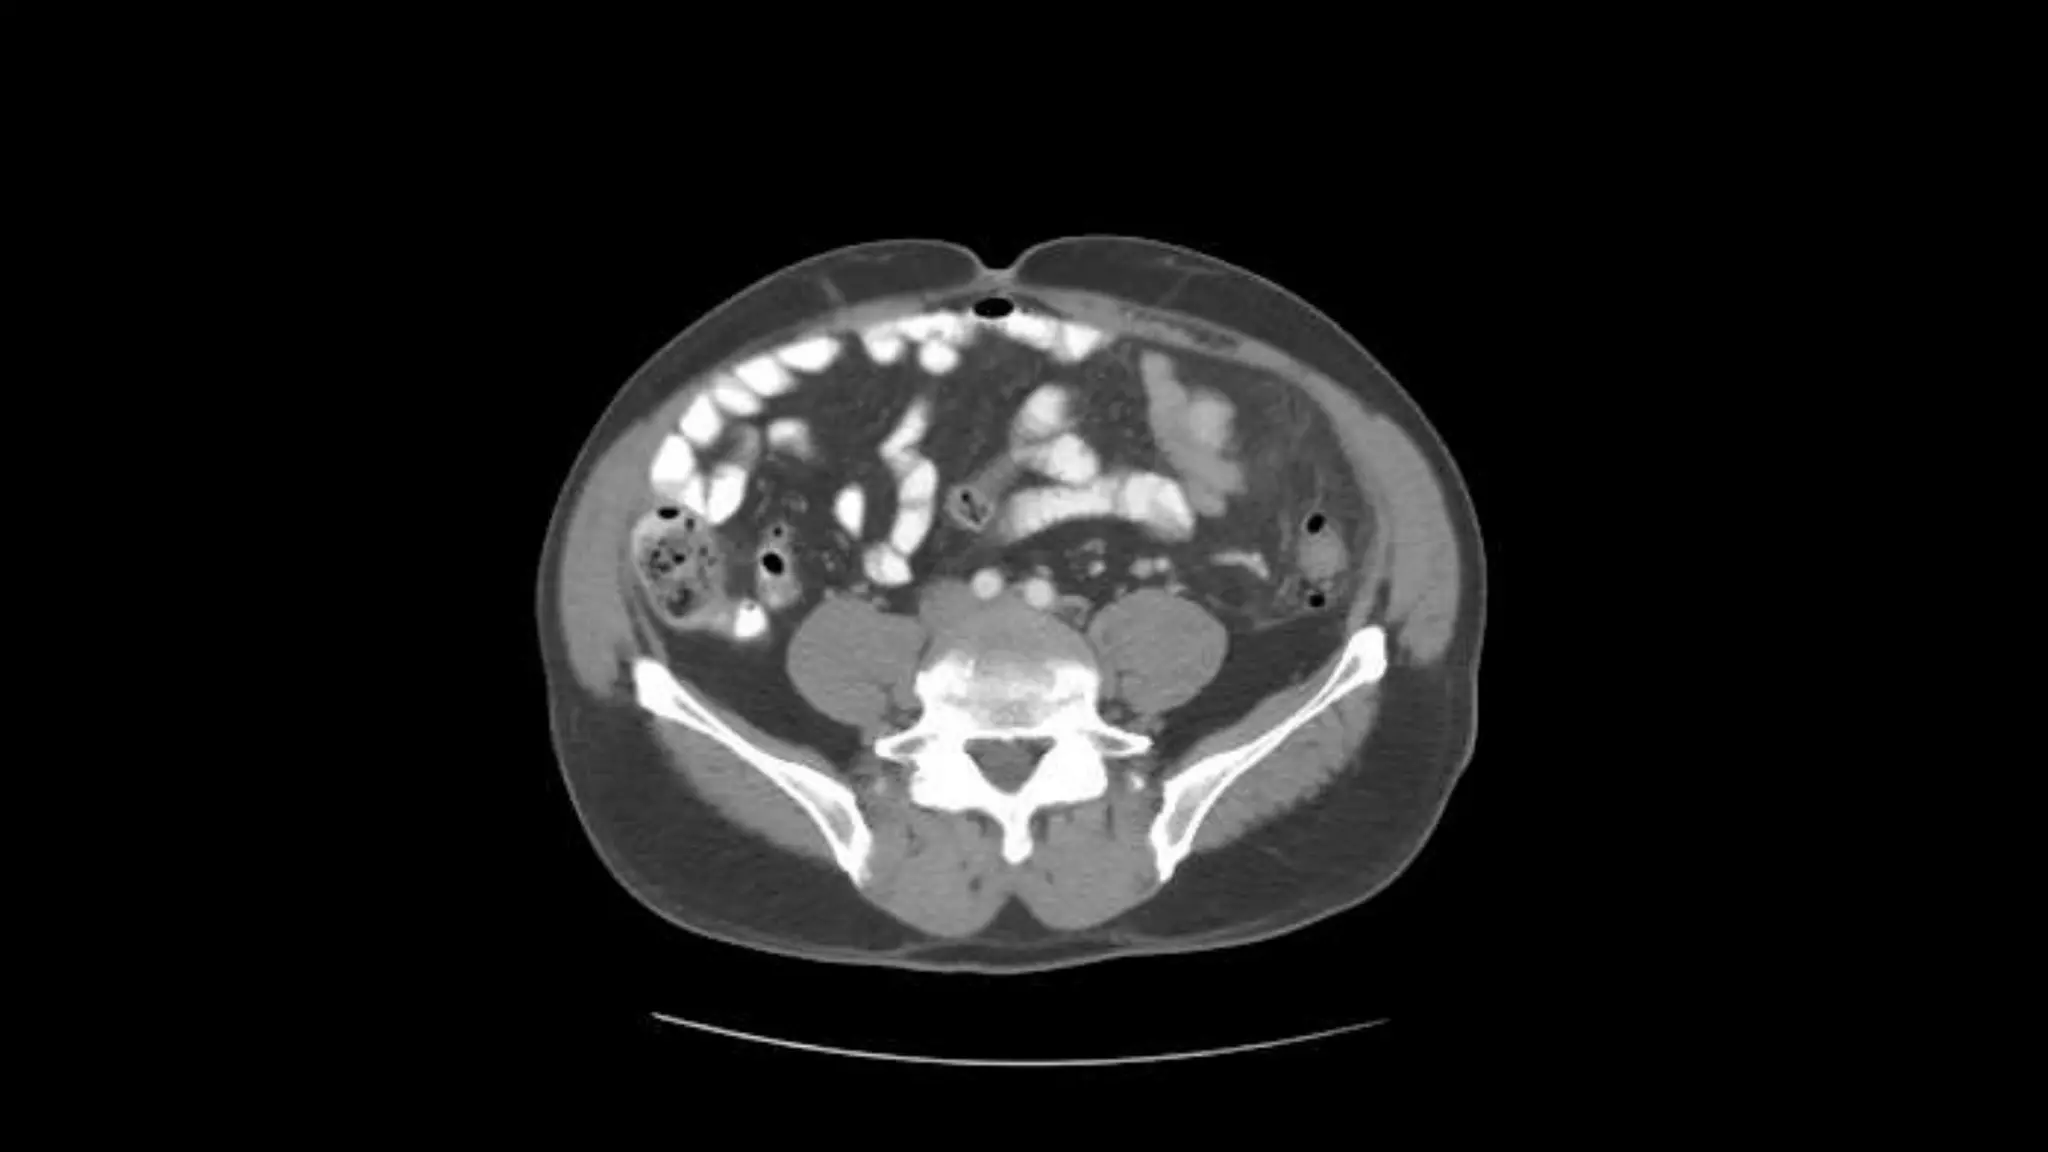

Aorta bifurcates into common illiac arteries

Appendix is noted coiling in Rt. Lower quadrant

Note air in lumen on adjacent scans

Psoas

muscles